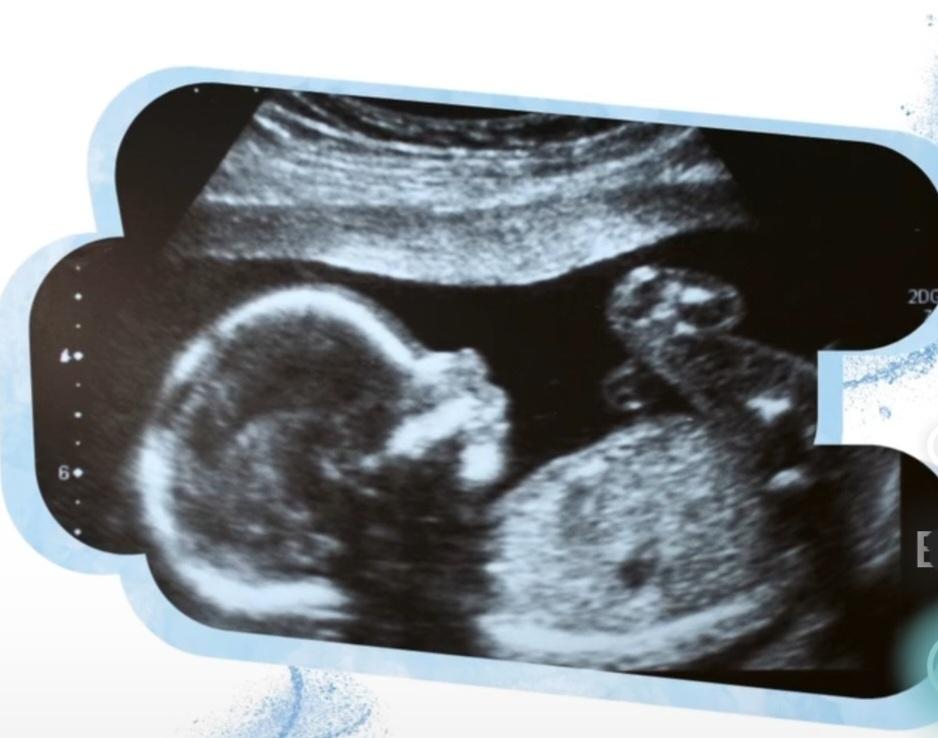

11-14 gebelik haftasında kombine tarama testi ve erken fetal anomali taraması

18- 23 gebelik haftasında fetal anomali taramasına yönelik ultrasonografi

28- 32 gebelik haftası fetal büyüme ve gelişim değerlendirilmesi